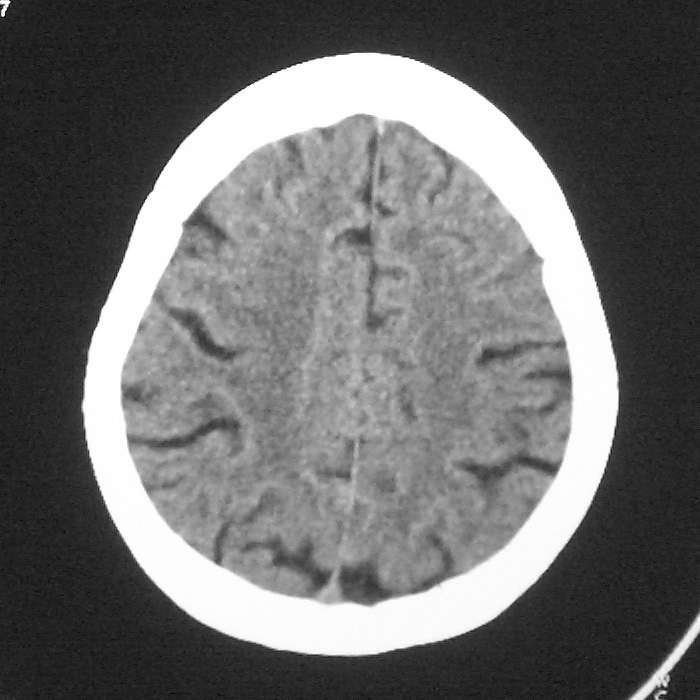

f,70y,口角歪斜、流涎、吐词不清三天

左侧大脑基底节区点状低密度影,边缘清楚,左侧腔梗或软化灶,没什么问题啊?

症状这么明显的话一般不会是单纯面神经麻痹引起的,最好做个mri,如果确实没有问题的话才能考虑面神经麻痹,毕竟这两种病的治疗和预后不一样,这个病人还有脑白质疏松。

左侧半卵圆中心腔梗应当比较明确,右侧基底节好象不明显,不好说,做个mri明确吧

双侧多发腔梗

右侧基底,左侧半卵圆中心腔梗

1、右侧基底,左侧半卵圆中心腔梗。2脑萎缩。

左侧腔隙性梗塞灶,脑萎缩。

左侧基底节区示点状低密度灶,边界清楚,密度均匀,余所示无著变。

意见:腔隙性脑梗塞(左基底节区)

各位老师,报告这么写可以吗?右侧我没有看出来。

左侧半卵圆中心,右侧基底节腔梗。再加个脑萎缩吧

双侧多发腔梗 脑萎缩